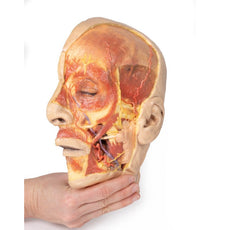

The face: On the right side of the head the parotid gland has been removed to reveal the facial nerve and all its branches (temporal, zygomatic, buccal, marginal mandibular and cervical) and demonstrate the spatial relations of structures embedded in the gland from superficial to deep (facial nerve, retromandibular vein, external carotid artery). In the surrounding region the temporalis, masseter and posterior belly of digastric are exposed, as are and the facial artery, transverse facial artery and superficial temporal artery. The facial vein and transverse facial vein are clearly visible uniting to form the common facial vein which is joined by the retromandibular vein to form the external jugular vein.

Viewed from the anterior aspect the face has been dissected to display some of the facial muscles around the mouth (buccinator [on the left], orbicularis oris and zygomaticus major). On the left side of the infratemporal fossa has been open to expose the medial and lateral pterygoids.

The lateral pterygoid is divided to show the mandibular division of the trigeminal nerve dividing into the lingual nerve and the inferior alveolar branch. Also on the left side the branches of the ophthalmic division of the trigeminal that supply the skin above the eyebrows and scalp (supraorbital [left only] and supratrochlear nerves [both sides]) are dissected. The submandibular gland is clearly visible below the mandible on both sides as are the facial arteries and veins as they course over the mandible.

This 3D print specimen preserves a series of features of the head and visceral column of the neck:The face: On the right side of the head the parotid gland has been removed to reveal the facial nerve and all its branches (temporal, zygomatic, buccal, marginal mandibular and cervical) and demonstrate the spatial relations of structures embedded in the gland from superficial to deep (facial nerve, retromandibular vein, external carotid artery). In the surrounding region the temporalis, masseter and posterior belly of digastric are exposed, as are and the facial artery, transverse facial artery and superficial temporal artery. The facial vein and transverse facial vein are clearly visible uniting to form the common facial vein which is joined by the retromandibular vein to form the external jugular vein.

Viewed from the anterior aspect the face has been dissected to display some of the facial muscles around the mouth (buccinator [on the left], orbicularis oris and zygomaticus major). On the left side of the infratemporal fossa has been open to expose the medial and lateral pterygoids.

The lateral pterygoid is divided to show the mandibular division of the trigeminal nerve dividing into the lingual nerve and the inferior alveolar branch. Also on the left side the branches of the ophthalmic division of the trigeminal that supply the skin above the eyebrows and scalp (supraorbital [left only] and supratrochlear nerves [both sides]) are dissected. The submandibular gland is clearly visible below the mandible on both sides as are the facial arteries and veins as they course over the mandible.